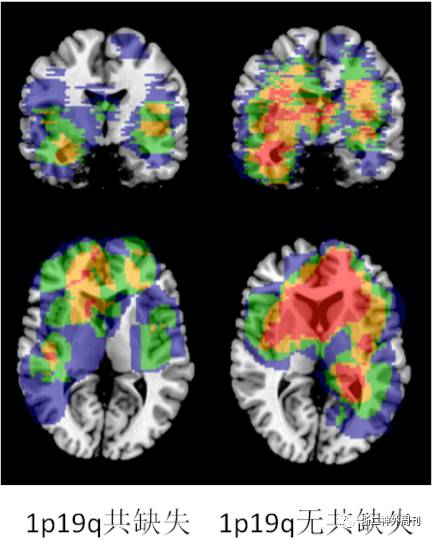

进一步我们分析肿瘤分子特征同肿瘤的位置关系。图4显示IDH基因突变同肿瘤位置的关系。图5显示TERT基因启动子突变同肿瘤位置的关系。图6显示染色体1p19q共缺失状态同肿瘤位置的关系。

图6. 不同1p19q共缺失状态的肿瘤的位置分布特征。